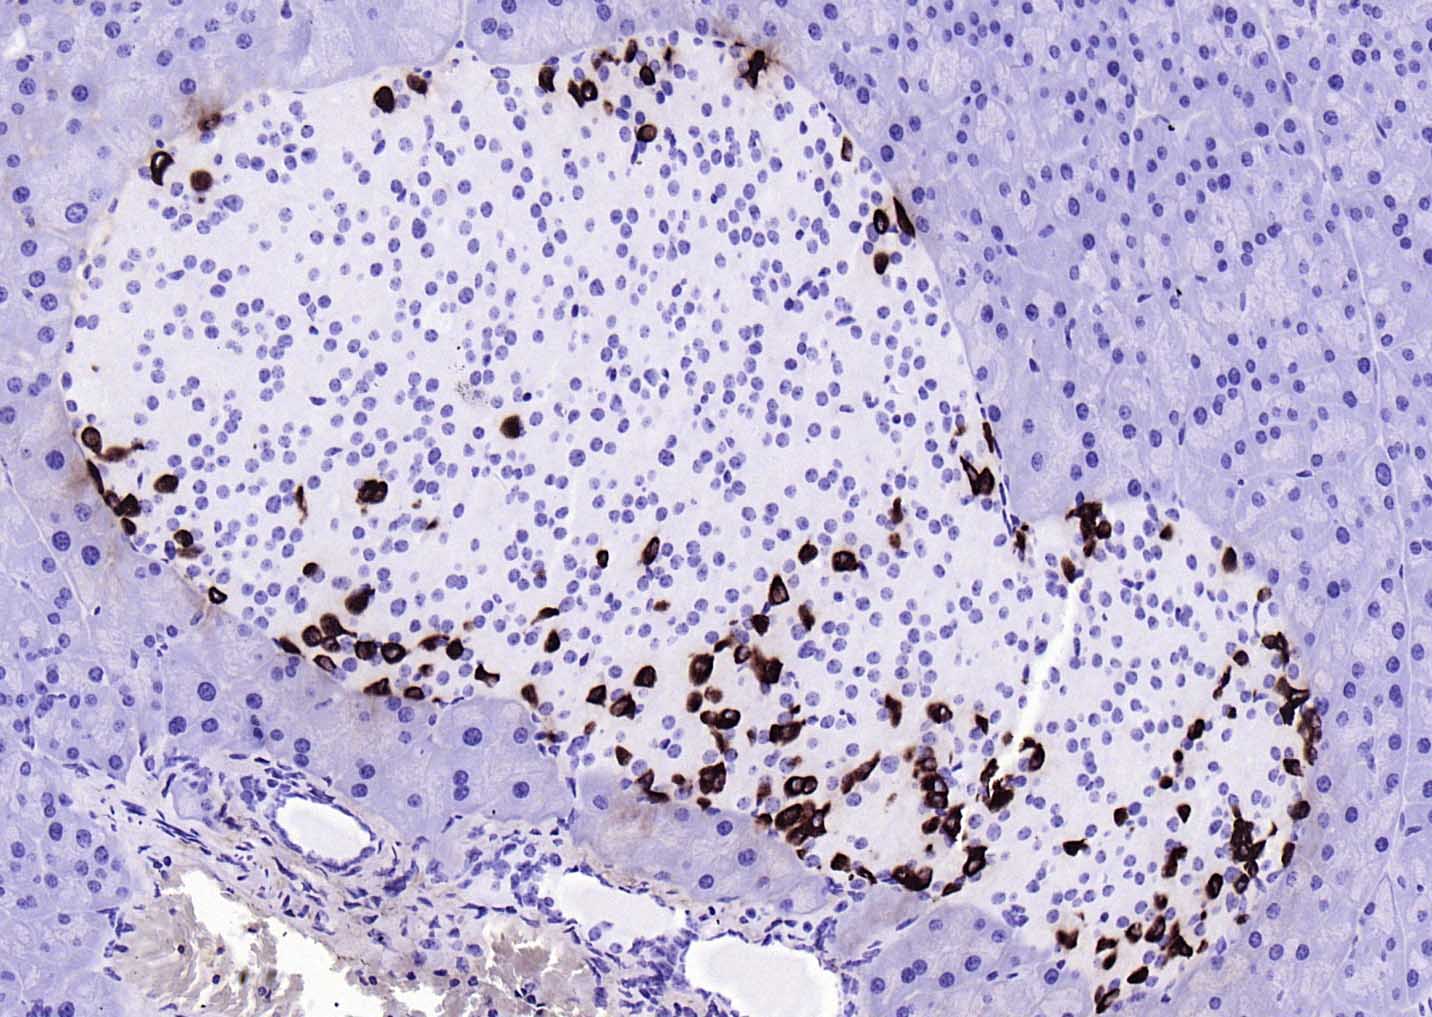

| 英文名称 | GLP-1(1G9) Mouse mAb |

| 中文名称 | GLP-1单克隆抗体 |

| 产品应用 | IHC-P=1:100-500, IHC-F=1:100-500, IF=1:100-500 Not yet tested in other applications. |

| 交叉反应 | Human, Mouse, Rat |

| 组织特异性 | Glucagon is secreted in the A cells of the islets of Langerhans. GLP-1, GLP-2, oxyntomodulin and glicentin are secreted from enteroendocrine cells throughout the gastrointestinal tract. GLP1 and GLP2 are also secreted in selected neurons in the brain. |

| {IHC-P} | {1:100-500} |

| {IHC-F} | {1:100-500} |

| {IF} | {1:100-500} |